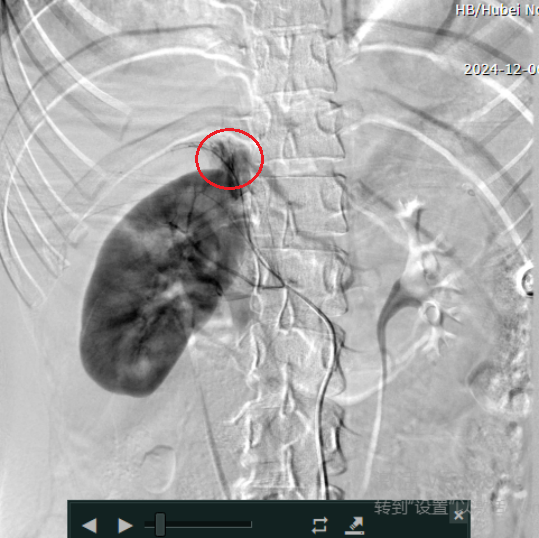

占必兴立即联系放射科主任刘良进,二人争分夺秒,就如何既能迅速止血救命、又能保住患者肾脏紧急讨论,最终制定了创新介入手术方案——超选择性肾动脉栓塞术。通过微小的导管直达肾脏受损血管,精准栓塞出血点,既有效控制出血,又最大限度保留肾脏功能。

术前

方案一经确定,手术立即启动。介入室内,泌尿外科团队与放射科介入团队密切配合,凭借丰富的经验和精湛的技术有条不紊地置入导管、精准定位、栓塞……手术圆满完成,年轻患者珍贵的肾脏得以保全。当医护人员把结果告诉患者奶奶时,年迈的奶奶再次流下眼泪。